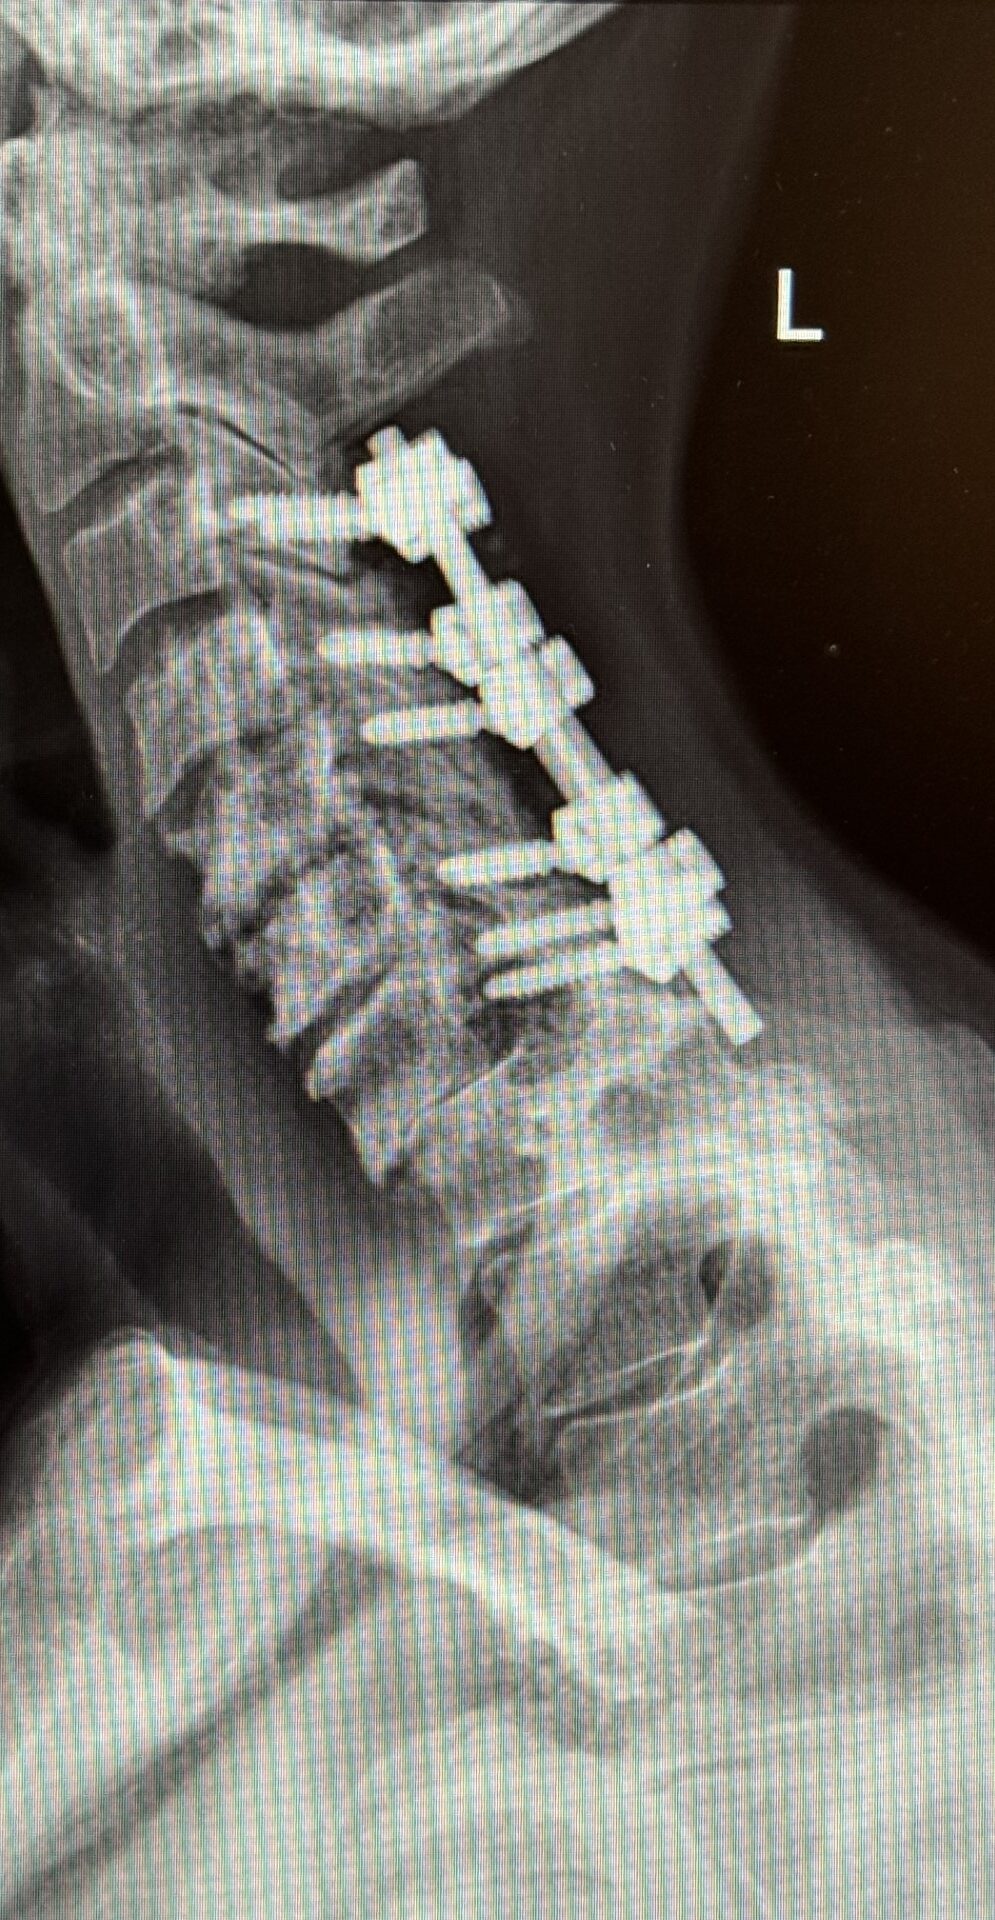

The patient is a 61-year-old female with a history of rheumatoid arthritis. She is 2-1/2-years status post C3-C7 laminectomy with posterior instrumentation and fusion. This procedure was performed to treat multilevel disc herniations with spinal cord compression following a motor vehicle accident.

She did well for several years, but then developed new onset of intractable neck pain with radiation to both upper extremities. She also had difficulty holding her head up.

Her rheumatologist ordered an x-ray which showed anterolisthesis of C7-T-1 with kyphosis and instability (Fig 1 right).